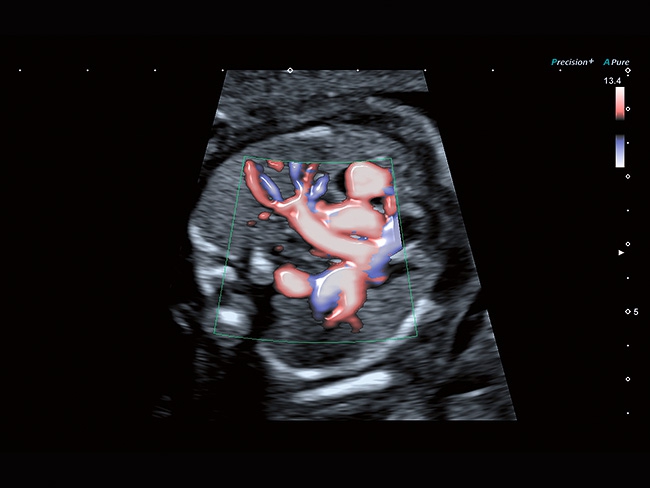

Aplio a550 может работать с линейным матричным датчиком и поддерживает новейшие монокристаллические датчики. Также Aplio a550 поддерживает большое количество дополнительных опций, таких как - SMI, Компрессионная эластография, Эластография сдвижной волны, Smart Fusion, исследования с использованием контраста (CEUS), 3D реконструкции в реальном времени (4D), функции автоматической оценки подвижности миокарда и фракции выброса.

• Fly Thru. Виртуальная эндосонография обеспечивает построение трехмерной модели полостей, протоков и сосудов в рельном времени, облегчает организацию инвазивных процедур и динамических исследований. Посредством Fly Thru можно установить шунты и стенты, проводить точные оперативные вмешательства.